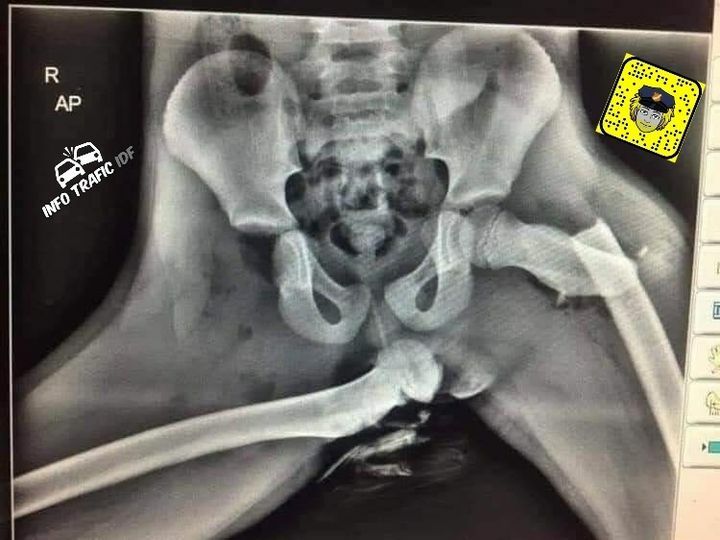

Voici une radiographie post accident après que l'airbag se soit déclenché

Si vous en connaissez montrez leurs !